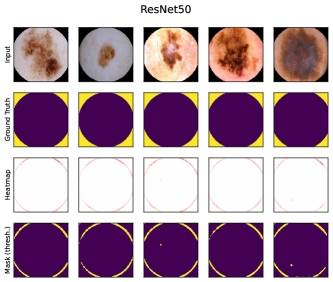

6.4 Spatial Bias Localization

To spatially localize biases in input space with CAVs, we compute local explanations for the element-wise product of latent activations and concept direction (see Eq. 2). We use the controlled artifacts, specifically timestamp (HyperKvasir) and micropscope (ISIC2019) with ground truth concept localization masks for evaluation. We compute (1) the percentage of relevance within the ground truth mask and (2) the Jaccard index, or Intersection over Union (IoU), of the binarized localization mask with the ground truth. In Fig. 9, we report both metrics using CAVs computed on different layers of VGG16 and ResNet50. The layer choice for concept representations is key, as for example middle layers perform better to localize timestamps and earlier layers are more effective to localize the microscope. In comparison with Fig.7, we find that the optimal layer for bias localization may differ from the one for sample retrieval. Interestingly, the IoU for the microscope artifact is consistently low, as models primarily focus on the border of the circle instead of the entire area, as indicated by qualitative results in Appendix A.6.3. Unlike artifact relevance, the IoU metric also measures how much of the expected areas the computed mask does not cover.